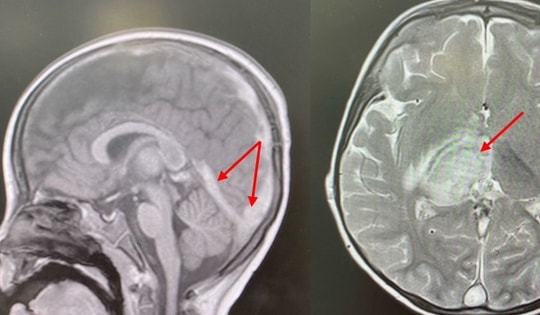

Bé 13 tuổi bất ngờ đột quỵ, hôn mê sâu khi đang tập văn nghệ ở trường

Bé 13 tuổi được cứu sống ngoạn mục sau khi bị đột quỵ do dị dạng mạch máu não vỡ, đây là căn bệnh hiếm gặp, có nguy cơ tử vong cao ở trẻ em nếu không được xử lý kịp thời.